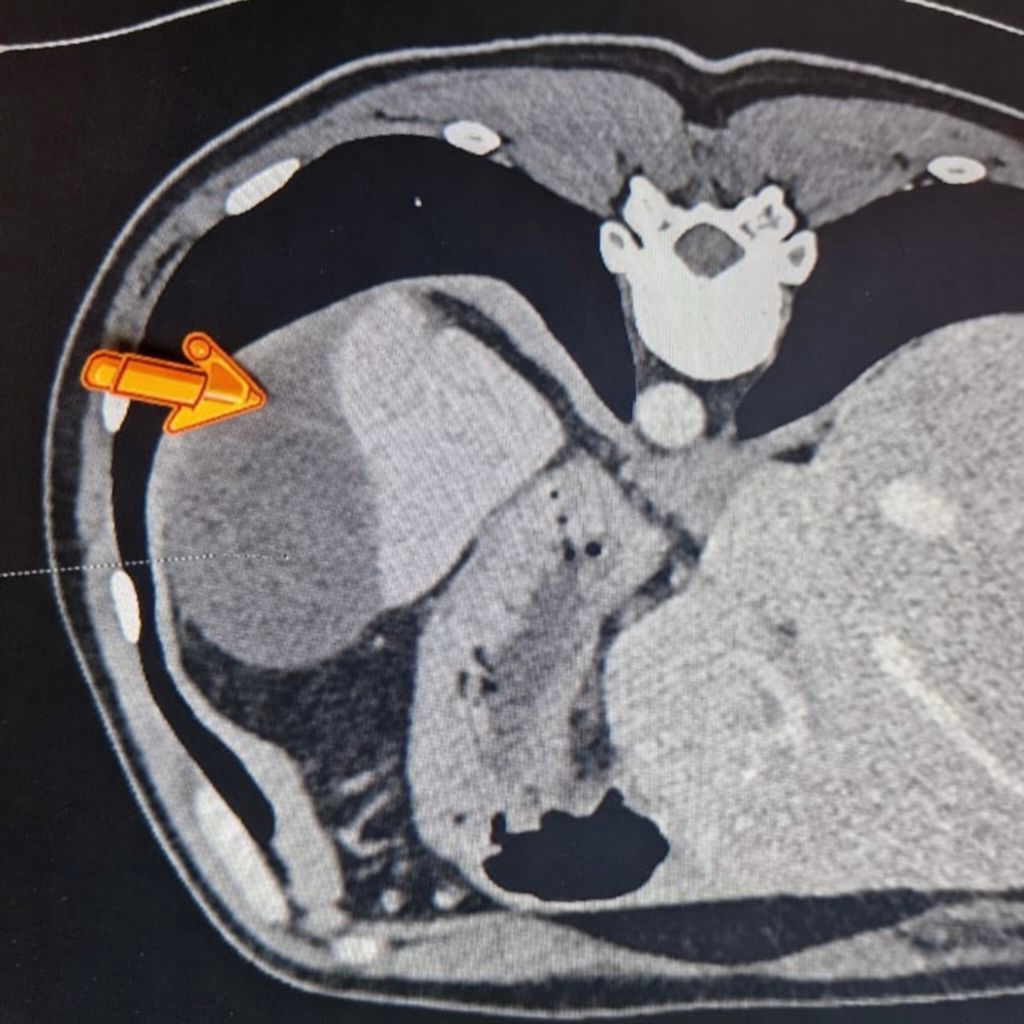

Дані спіральної комп’ютерної томографії показали розрив селезінки з формуванням великої гематоми. Фото: НВКМЦ

— Безумовно, підготовка до операції — це дуже важлива процедура. Ми виконали спіральну комп’ютерну томографію, що нам дозволило чітко побачити розмір цієї гематоми. І ми навіть знайшли той розрив селезінки на діафрагмальній поверхні, який призвів до такої кровотечі з формуванням гематоми.